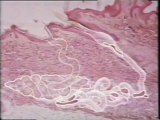

Olor maternal y lactancia_ Glandulas de Montgomery

El olor materno dirige al recién nacido hacia el pecho.

Olor maternal y lactancia: Glandulas de Montgomery